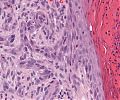

A63 Basaliom

Basaloide Tumorformationen mit palisadenartiger Begrenzung der Zellnester.

A63 Basaliom

Tumorinfiltration, ausgehend von der Epidermis

Basaliom_A63.png

Erkennbar sind Tumorzellnester mit pallisadenförmiger Anordnung der Tumorzellem am Rand